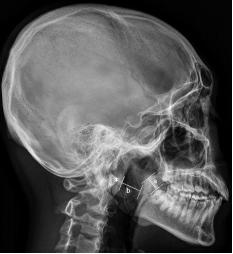

문 2. 수면 무호흡 환자에서 찍는 두부 X선 촬영(cephalometry)에 대한 설명 중 틀린 것은?

① 수면 무호흡 환자에서 두부 X선 사진은 CT나 MRI에 비해 부정확하지만, 간단한 계측을 통해 평가할 수 있는 지표로 인정된다.

② 수면 무호흡이 심한 환자에서 일반적으로 연구개의 두께는 두껍고 기도 크기는 작은 것으로 나타난다.

③ 비강 수술에 따른 기도 크기 변화는 중등도 이상의 수면 무호흡 환자에서 효과가 크며, 경도의 수면 무호흡 환자에서는 비강 수술로 인한 기도 크기 변화는 없다.

④ 아래 사진에서 a는 soft palate thickness를, b는 retropalatal posterior airway space를 나타내며 C1 척추뼈 앞결절(anterior tubercle)에서 인두 기도의 음영에 직각으로 선을 그어 만나는 부위에서 측정한다.